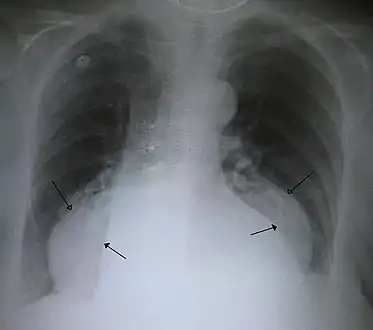

A large hiatal hernia on chest X-ray marked by open arrows in contrast to the heart borders marked by closed arrows